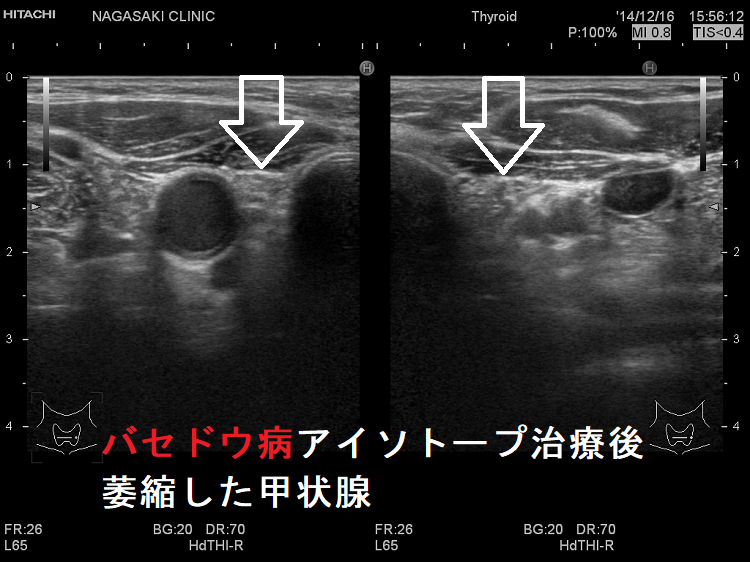

(写真)バセドウ病 アイソトープ治療後8年 超音波(エコー)画像;甲状腺は萎縮しています。

バセドウ病 アイソトープ治療後8年 超音波(エコー)画像

アイソトープ治療後、萎縮した甲状腺